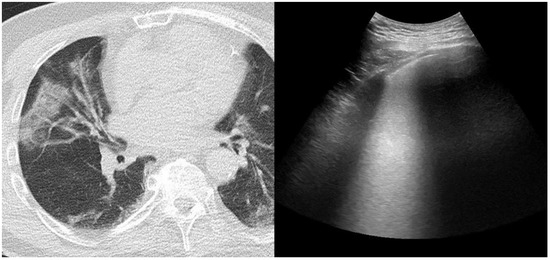

:1. Introduction

2.3. Chest Computed Tomography and Score Assessment

2.4. Lung Ultrasonography and Score Assessment